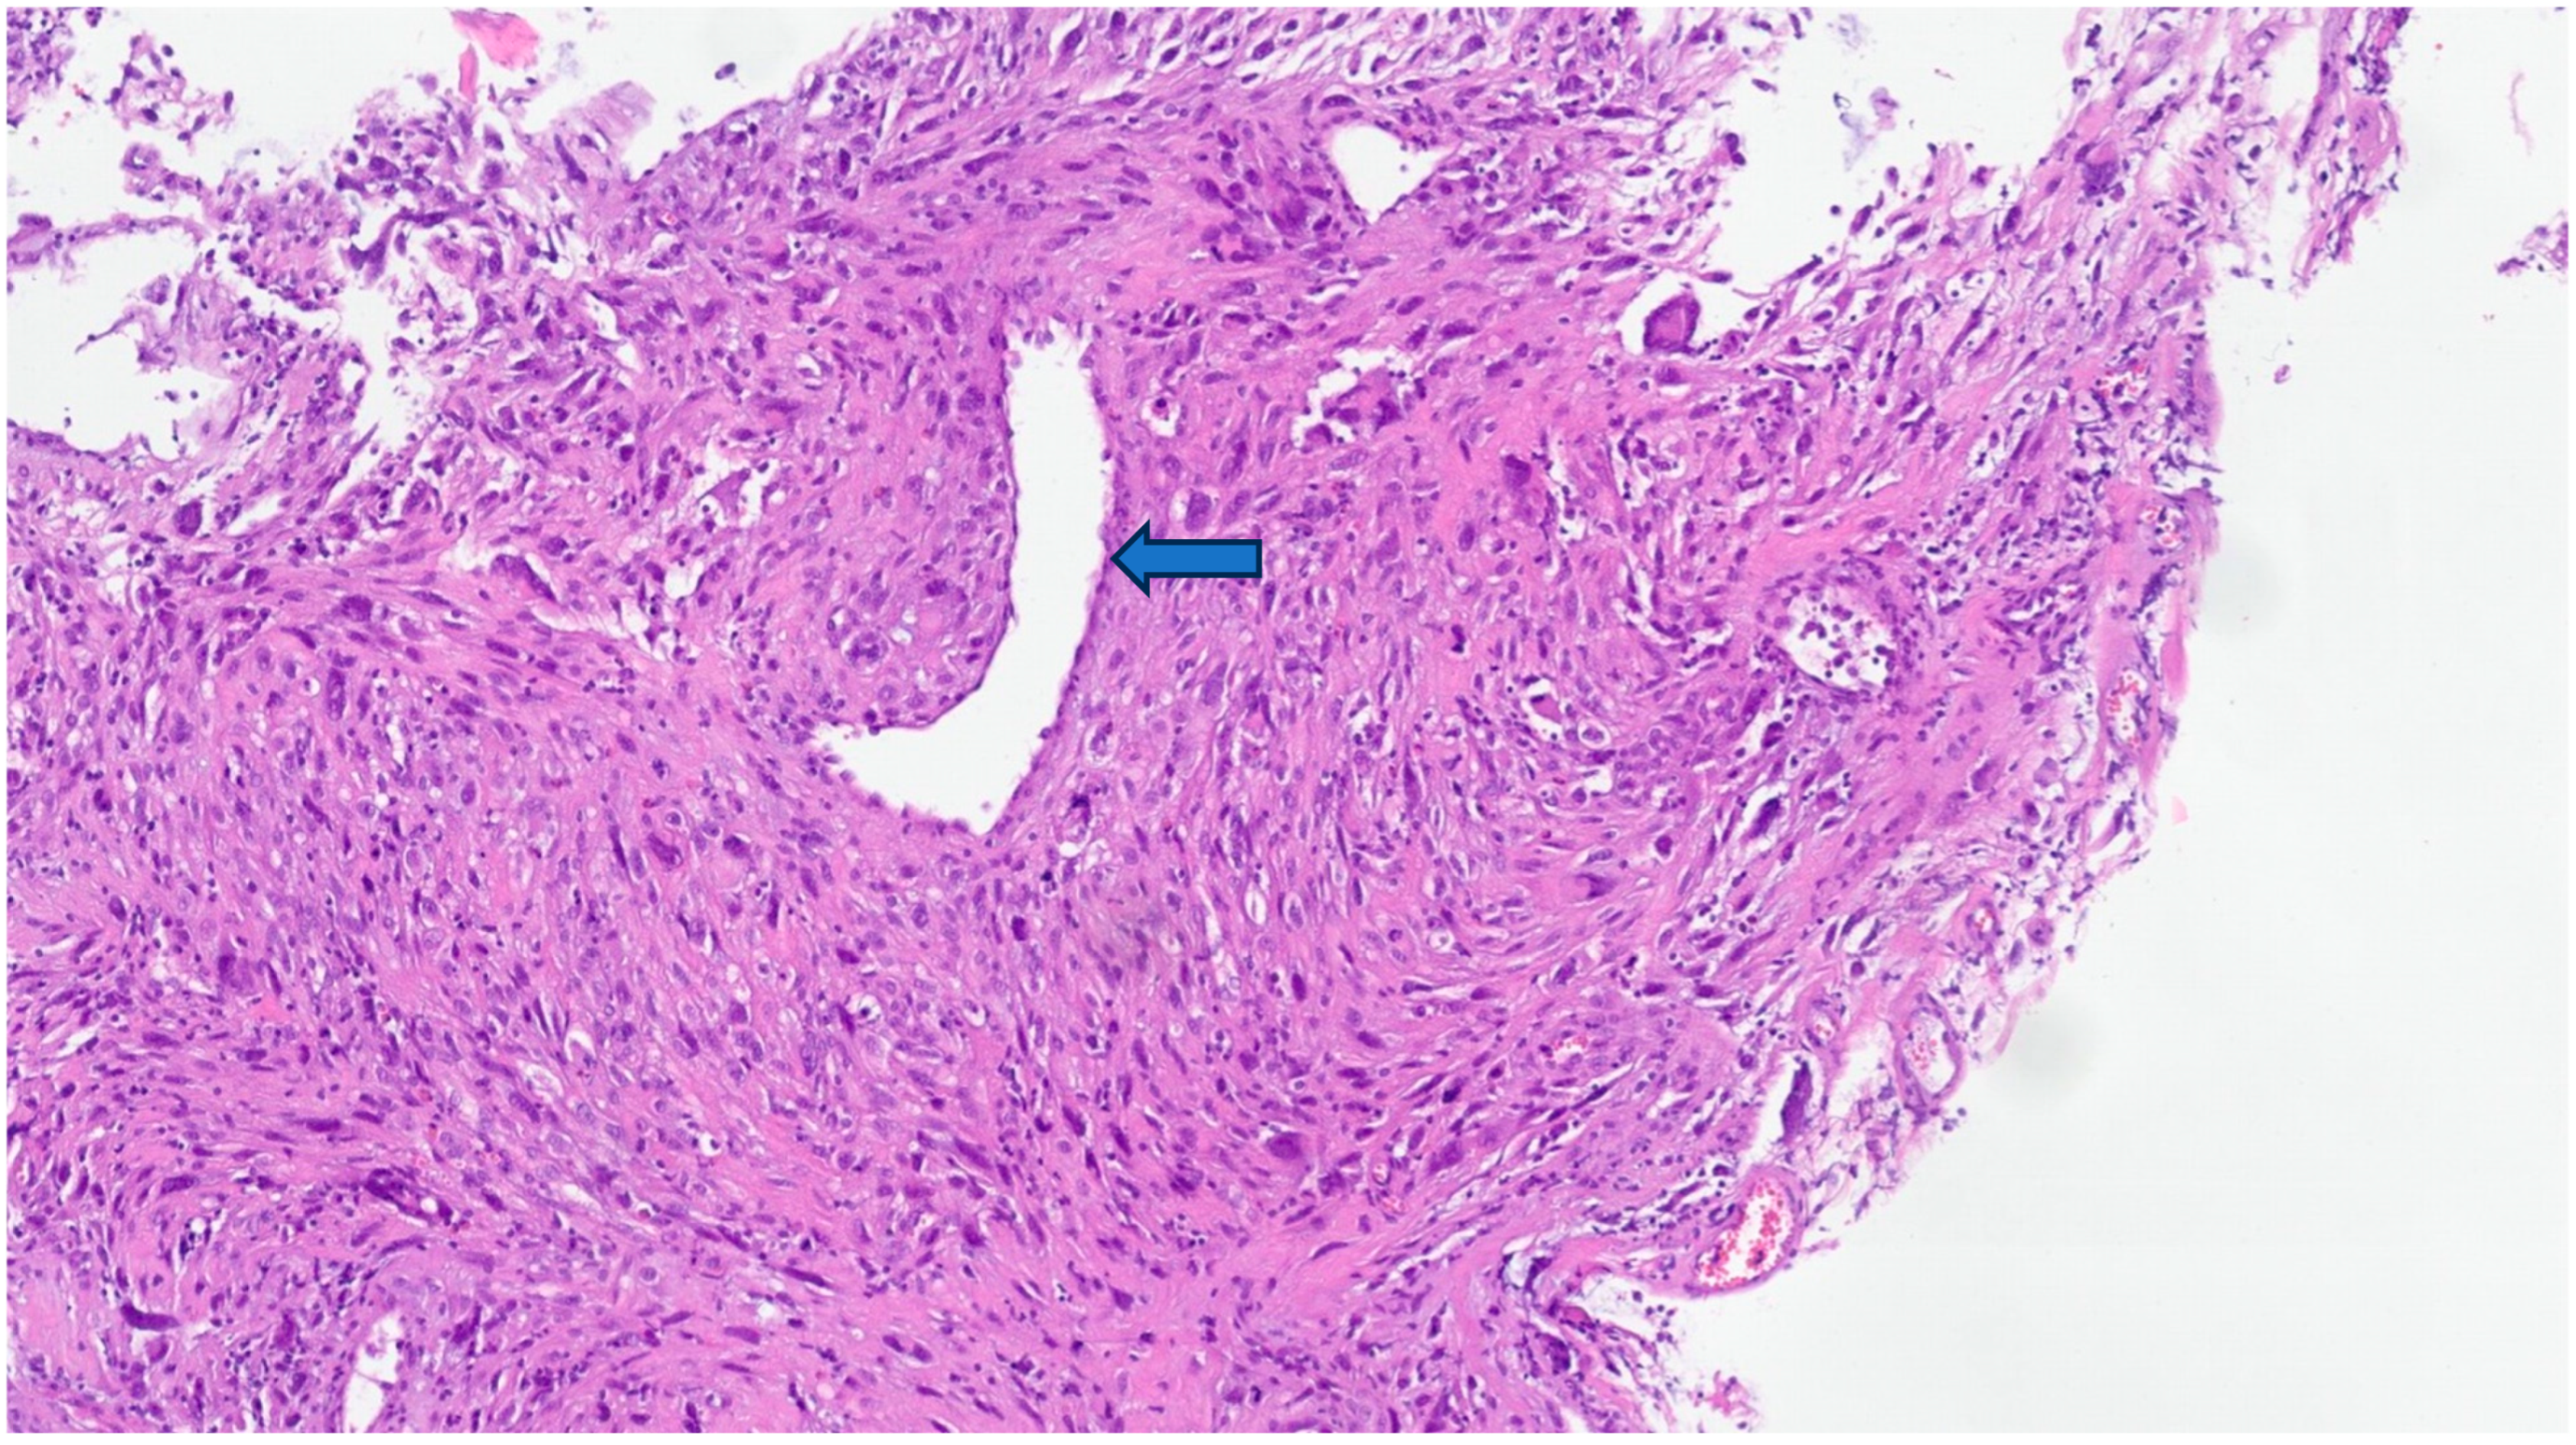

6. Gross and Histologic Features